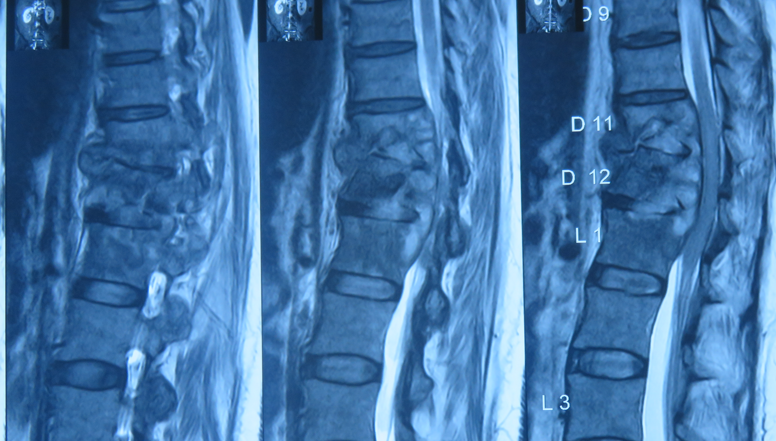

MRI scan is the most accurate method to detect infection early. Blood tests and CT-guided biopsy help identify the exact organism.